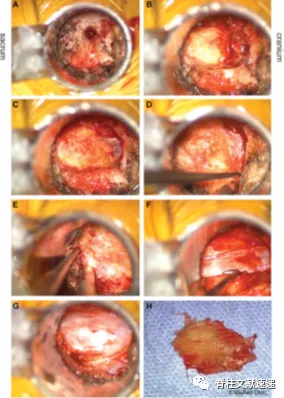

黄韧带整块切除

图3通过管牵开器的术中照片:(A)L4右关节间部对接点,为L4-L5经椎间孔腰椎体间融合术做准备。(B)用高速钻头接近椎板腹侧黄韧带的连接点,切除L4板的三分之二。黄韧带从其与对侧韧带的中线连接处分离,可见中线硬膜外脂肪垫。(C)继续椎板切除使上椎板上的韧带止点脱离。(D)分离黄韧带的上外侧角,L4神经根的腋窝在这个解剖标志下。(E)用咬骨钳从下椎板的上侧面取下少量的骨,以分离韧带的下附着体。(F)黄韧带的上、内、下附着被释放后,黄韧带向外侧翻转,露出硬膜囊。(G)用咬骨钳释放黄韧带的外侧附着点,并将韧带移除。(H)全组切除后的黄韧带。